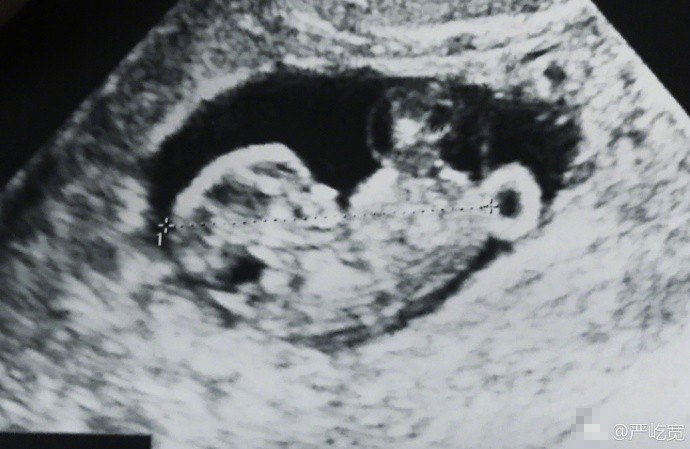

严屹宽还晒出了一张B超照片和夫妻俩的合照。照片中,杜若溪对着镜头比耶,而严屹宽看着自己的爱妻,虽然戴着墨镜,但是看起来满面笑容,宠溺十足。两人于2013年领证,2014年结婚,多年一直恩爱有加,经常放闪。现在两人要有了第一胎宝宝,恭喜恭喜。